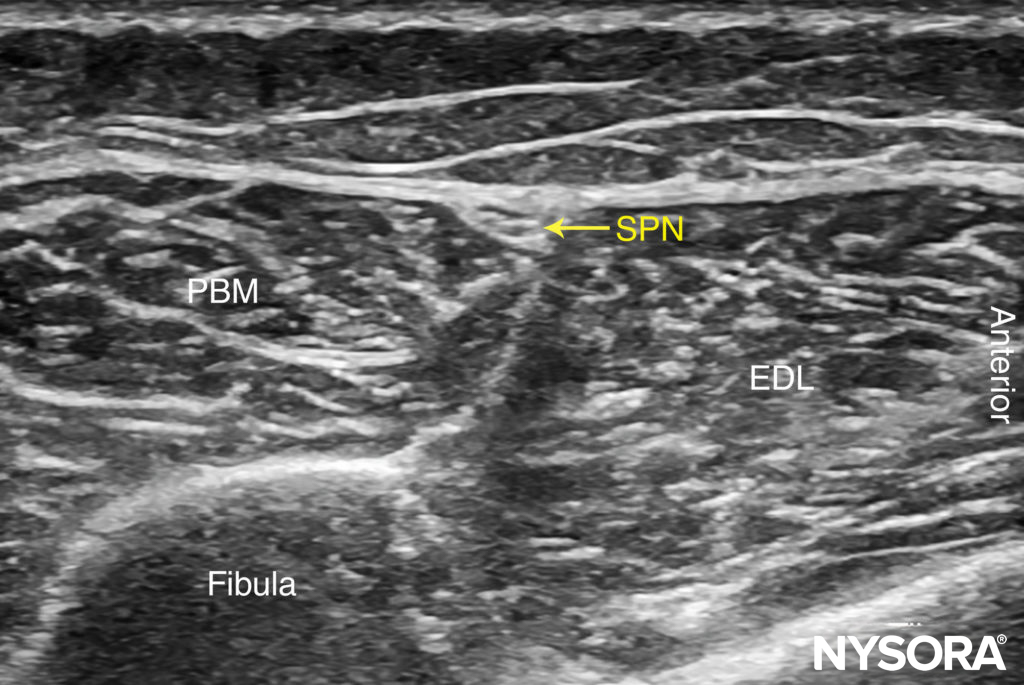

FIGURE 9. US anatomy of the superficial peroneal nerve (SPN). PBM, peroneus brevis muscle. (Reproduced with permission from Hadzic A: Hadzic’s Peripheral Nerve Blocks and Anatomy for Ultrasound-Guided Regional Anesthesia, 2nd ed. New York: McGraw-Hill, 2011.)

The superficial peroneal nerve innervates the dorsum of the foot. It emerges to lie superficial to the fascia 10–20 cm above the ankle joint on the anterolateral surface of the leg and divides into two or three small branches. A transducer placed transversely on the leg, approximately 5-10 cm proximal and anterior to the lateral malleolus, will identify the hyperechoic nerve branches lying in the subcutaneous tissue immediately superficial to the fascia (Figures 7, 8, and 9). To identify the nerve proximal to its division, the transducer can be traced proximally until, at the lateral aspect, the extensor digitorum longus and peroneus brevis muscle can be seen with a prominent groove between them leading to the fibula (Figure 10).

Superficial Peroneal Nerve

The superficial peroneal nerve is located in this groove, just deep to the fascia. Once it has been identified at this more proximal location, the nerve can be traced distally to the ankle or it can be blocked at this level. Because the superficial nerves are rather small, their identification with US is not always possible.